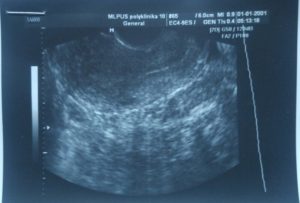

Трансабдоминальный метод

Данный вид ультразвукового исследования является более безопасным, так как делается через переднюю стенку живота, однако, к сожалению, менее точным. Диагностировать появление плодного яйца с помощью данного метода можно только на 5-й ее неделе, а зафиксировать сердцебиение – на 6-7-й.